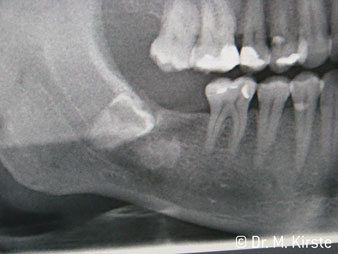

Elegir el ángulo de 45º ofrece múltiples ventajas de uso. Los odontólogos dedicados a cirugía (para quienes se desarrolló principalmente esta pieza de mano) se percatarán de inmediato de que se puede trabajar de forma muy específica. En especial en la remoción de las muelas del juicio (Fig. 2), no es necesaria una gran abducción de las partes blandas en la zona del carrillo (Fig. 3). El diseño del cabezal de la pieza de mano, combinado con los suaves giros del cabezal durante la preparación, permite trabajar de forma rápida y segura en la zona retromolar.